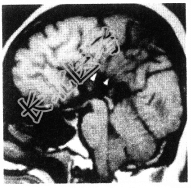

- [材料题] 患者,女性,41岁。智力低下,MRI结果如下图所示。

- 单项选择题1.可能的诊断是( )。

A、胼胝体缺如

B、脑裂畸形

C、灰质异位

D、结节性硬化

E、斯德奇-韦伯(Sturge-Weber)综合征

- 单项选择题2.关于该病的描述,错误的是( )。

A、常与其他畸形伴发,如前脑无裂畸形、Chiari畸形、胼胝体脂肪瘤等

B、均为全部缺如

C、矢状位显示最佳,无胼胝体结构

D、脑回放射状排列,指向侧脑室

E、影像学首选MR矢状面、冠状面